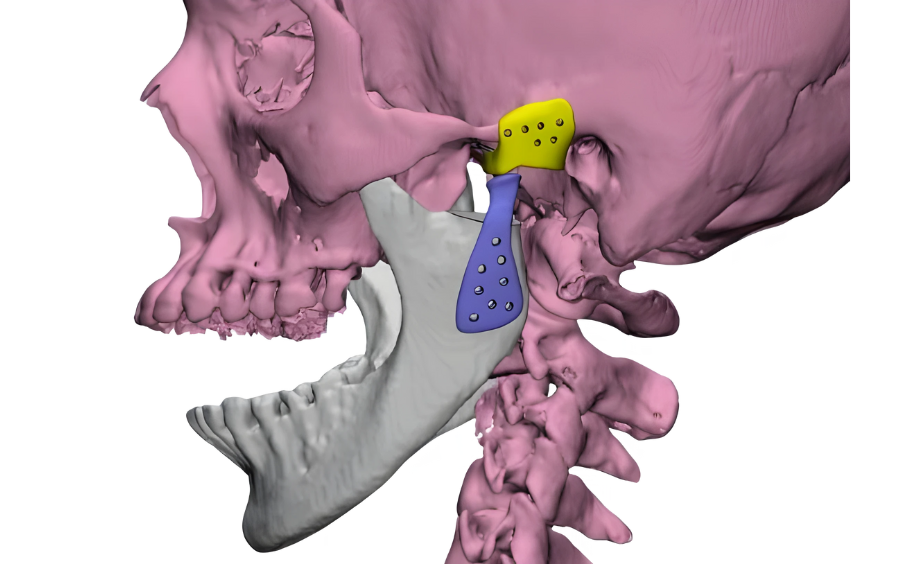

Based on the findings from the scans and 3D model, Dr. Bohra recommended TMJ replacement surgery. Dr. Bohra collaborated with the design team at 3D Incredible to create and place a patient-specific Temporomandibular Joint (TMJ) implant.

This innovative approach aimed to address both the aesthetic and functional aspects of TMJ reconstruction, utilizing advanced materials and tailored design techniques. Read more